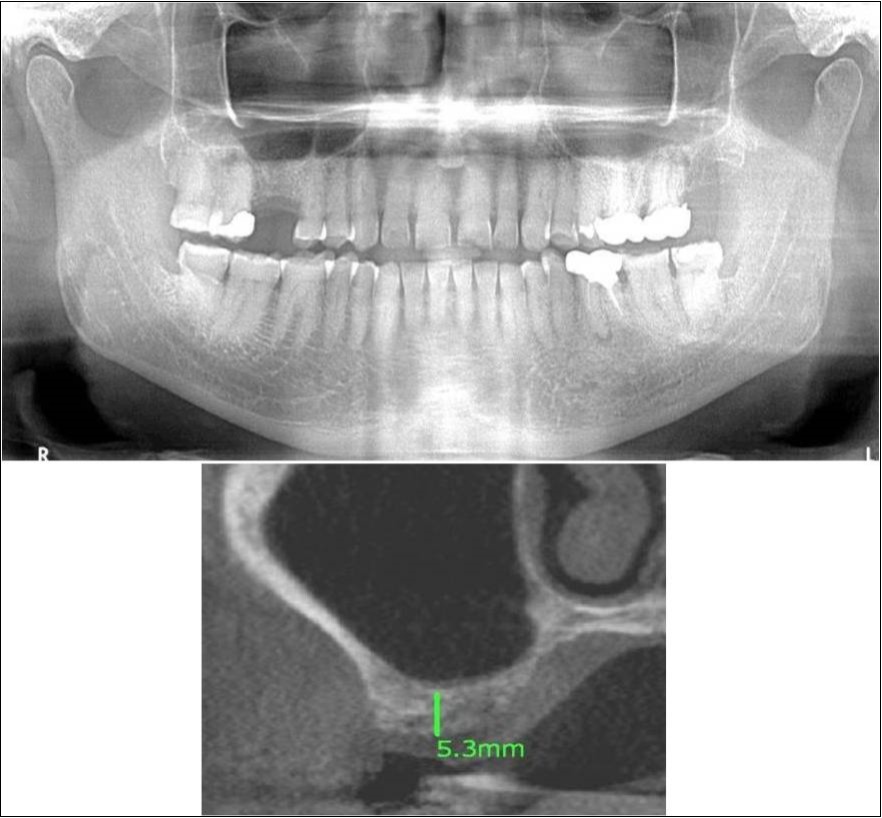

Figure 9.(a,b) Pre-treatment OPG and cross section of CBCT showing residual alveolar bone height for Case No.2

Figure 10.(a,b) Post-treatment OPG and cross section of CBCT showing residual alveolar bone height for Case No.2

A 42 years old male patient reported to the Department of Oral and Maxillofacial Surgery, D.A.P.M.R.V Dental College and Hospital with a chief complaint of inability to chew food because of missing teeth in upper right and left back tooth regions from past one year. The teeth were extracted an year ago because of gross loss of tooth structure and poor prognosis for root canal treatment. Patient was a hypertensive since 4 years and was on medication for the same. Patient did not give history of any existing sinus pathologies. All possible rehabilitative options were explained to the patient and a treatment plan of replacement of missing teeth with implant supported prosthesis using one dental implant in 17 region was finalized.

Clinical and Radiological Assessment:

1.Partially edentulous maxillary and mandibular arches with missing 17, 26, 45, 46;

2.Increased pneumatisation of right maxillary sinus;

3.Height of available bone- 6.6mm;

4.Transverse thickness of available bone (CBCT evaluation)- 11mm;

5.Inter-ridge space adequate to place implant (10mm).

Treatment:

Patient underwent the procedure of indirect sinus elevation using sinus osteotomes in relation to 17 region. Calcium phosphosilicate putty was dispensed as the graft material through the crestal osteotomy site to maintain the elevated sinus membrane followed by placement of a dental implant measuring 5 x 10mm under local anaesthesia and strict aseptic protocols .The implant was allowed to osseo-integrate for a period of six months during which the patient was followed-up periodically and was assessed for peri-implantitis, crestal bone loss and mobility. At the end of 6 months, a repeat CBCT scan was advised to evaluate the increase in bone height. (Figure 9a,b, pre-treatment; Figure 10a,b, post-treatment)